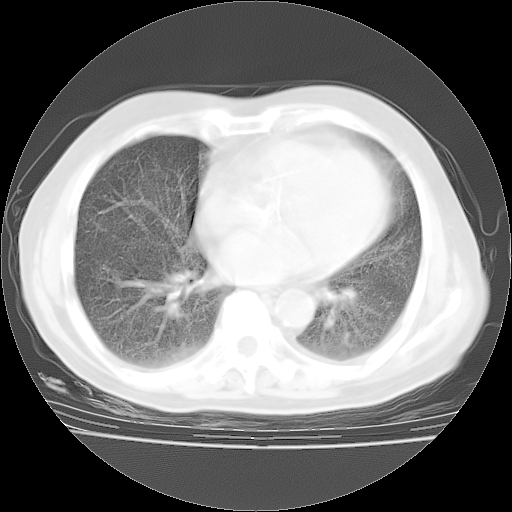

楼主| 发表于 2010-4-28 16:59 | 显示全部楼层

4月28日肺部CT——再次出现类似去年5月9日——透光度降低,(影像科认为)“间质性”改变。

1221483 1 .bmp

1221483 2 .bmp

1221483 3 .bmp

1221483 4 .bmp

1221483 5 .bmp